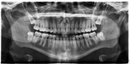

Diş hekimleri kök kalma riskini azaltmak için öncelikle detaylı radyografik incelemeler (panoramik röntgen, 3D tomografi) yaparak diş ve kök yapısını değerlendirir. Özellikle kırılgan, çürük veya şekli bozuk dişlerde dikkatli cerrahi teknikler uygularlar. Deneyimli hekimler, minimal travma prensibiyle çalışarak dişi bütün halinde çıkarmaya özen gösterirler.